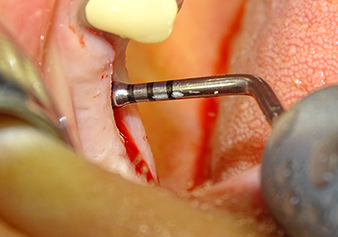

Implant bed preparation and augmentation

Following an intermediate check (Fig. 4) a further preparation step was performed (Fig. 5). Afterwards, the hydraulic Z35P instrument was used to lift the membrane to the desired position (Fig. 6 and 7). This was followed by further piezosurgical preparation of the implant bed, concluded with a rotary bur and shoulder milling cutter up to the implant diameter of 4.8 mm. Before the implant was inserted, the augmentation material (particle size approx. 0.8-1.6 mm) was introduced underneath the Schneiderian membrane (Fig. 8).